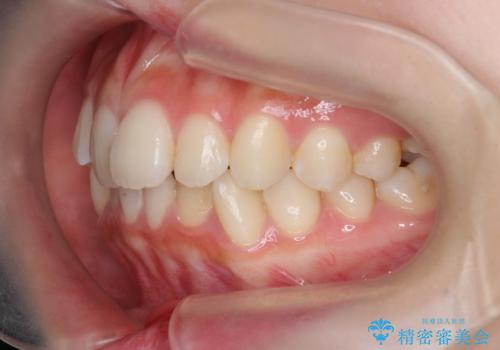

インビザラインライトで行う短期マウスピース矯正治療

- 前歯のガタつきを並べたいたいと、矯正治療を希望され来院されました。

とにかく短期間で前歯だけの治療を行いという希望が強く、全体矯正と前歯だけの部分矯正の仕上がりのイメージを確認したのち14枚のマウスピースで前歯のみの矯正治療を行っていくこととしました。

インビザラインライトは軽度なガタつきや傾斜の改善に用いられる全14枚のマウスピース矯正です。